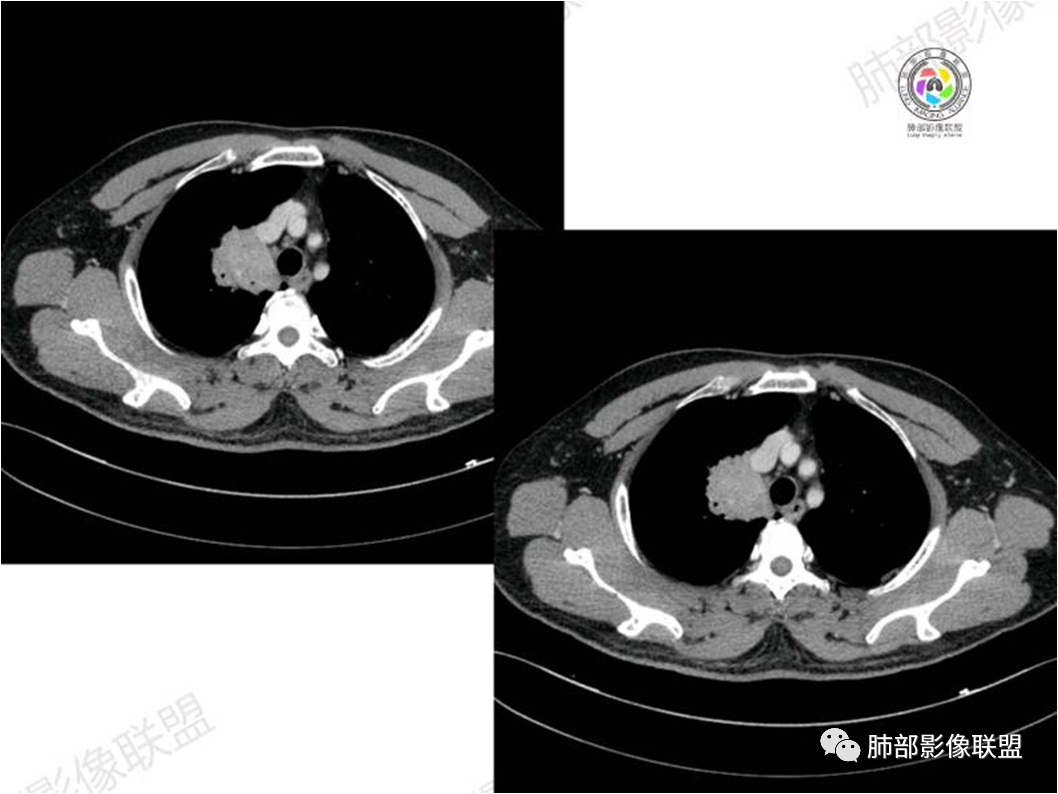

胸部CT:

中年男性,偶有咳嗽,右肺上叶近纵膈旁占位,内可见僵硬的支气管和小空泡征,病灶边缘可见分叶,毛刺,增强病灶中度以上不均匀强化,可见血管造影征,考虑恶性病变,腺癌可能性大。

右肺上叶纵隔胸膜侧一实性肿块,与纵隔胸膜宽基底相连,局部脂肪间隙消失,形态欠规则,内部可见多个小空泡,平扫密度尚均匀,增强后可见点条状强化,内部穿行血管,周围肺组织干净,纵隔淋巴结略肿大,男性44岁,只有咳嗽,考虑恶性肿瘤,腺癌,鳞癌。鉴别结核,OP,炎性假瘤。

右肺上叶近纵膈旁肿块,密度均匀,边缘分叶,毛刺,气管受压变窄,不均匀强化,可见血管造影征,考虑淋巴瘤,鉴别炎性假瘤。

中年男性,右肺上叶纵隔旁软组织肿块,边缘膨隆、毛糙,可见多发分叶,支气管穿行,部分截断,增强后密度欠均匀,纵隔内见多发小淋巴结,首先考虑恶性,腺癌,鉴别淋巴瘤

中年男性,右肺上叶纵隔旁肿瘤,稍膨隆,有毛刺,支气管穿行,远端闭塞,强化均匀,血管走行尚可,考虑淋巴瘤可能性大(支气管远端闭塞,不太符合),鉴别腺癌(气管穿行后闭塞,不太符合),op(病灶稍膨隆)

患者中年男性,咳嗽就诊,无其他不适。胸部CT:右肺上叶尖段上纵膈旁肿块,边界清楚,边缘光滑,内见支气管受压变窄,伴阻塞性改变,增强均匀强化,见血管造影征。综合考虑恶性病变,小细胞肺癌或淋巴瘤。气管镜活检应能明确。

中年男性,右肺上叶纵隔旁实性病灶,边缘有彭隆,有平直,有分叶,有尖角,病灶边缘中心可见支气管征,周围少许磨玻璃,边缘模糊,增强后动脉期病灶可见强化血管影,渐进性强化,临近血管界限清晰。考虑炎性病灶,普通炎性肉芽肿?结核?炎性肌纤维母细胞瘤?鉴别腺癌,淋巴瘤